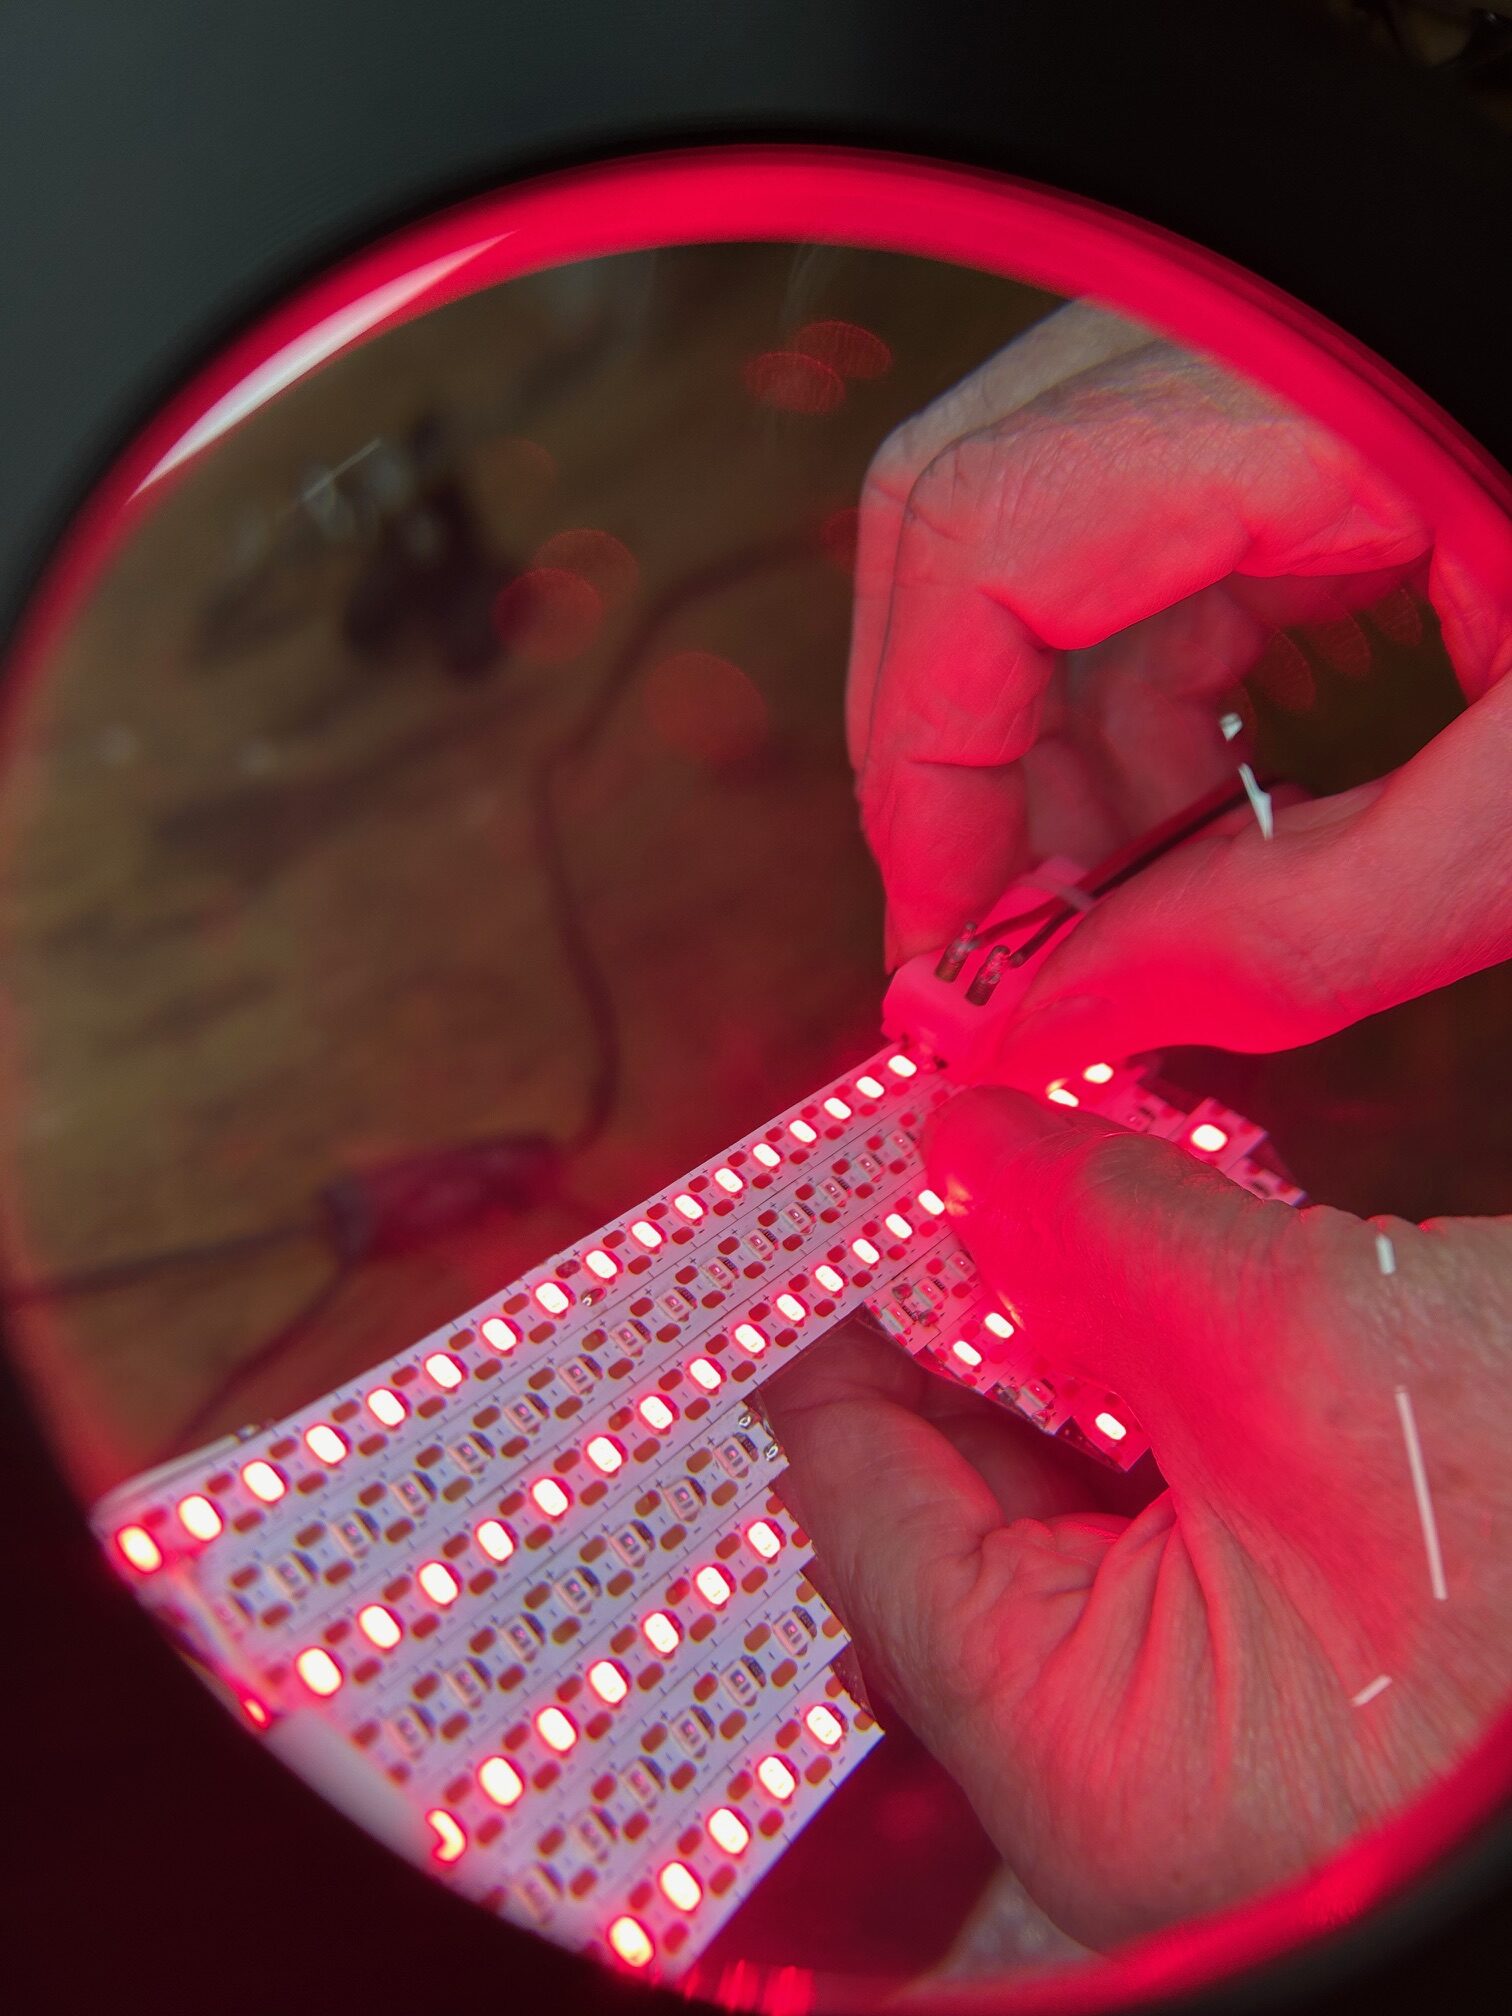

LLLT was conducted on patients at Dankook University Hospital upon the scheduled visits of each patient. Light irradiation was performed with a LED-based array matrix module with 5 planar panels. For the first 1 min of irradiation a wavelength of 590 nm in continuous wave and an irradiance of ≈ 50 µW/cm² scanned panel by panel for 1 s per panel, giving a fluence of ≈ 50 µJ/cm². At the end of that minute, 830 nm was delivered from all 5 panels at an irradiance of 100 mW/cm² for 10 min in continuous wave mode. The energy density over the entire near field area (encompassing the entire face and orbital area) was therefore ≈ 60 J/cm² per session.

Reports have suggested that the above parameters with the 830 nm LED-based approach have been safe and effective in general for wound healing and as an adjunctive approach to other aesthetic procedures. Specifically, the same device as used in the present study has been proven safe and effective for treating wounds on the face around the orbit and for effective and safe treatment of acute herpes zoster ophthalmicus. No serious adverse events were observed. The use of LED-LLLT for the treatment of dry eye and MGD appears to be safe and beneficial.